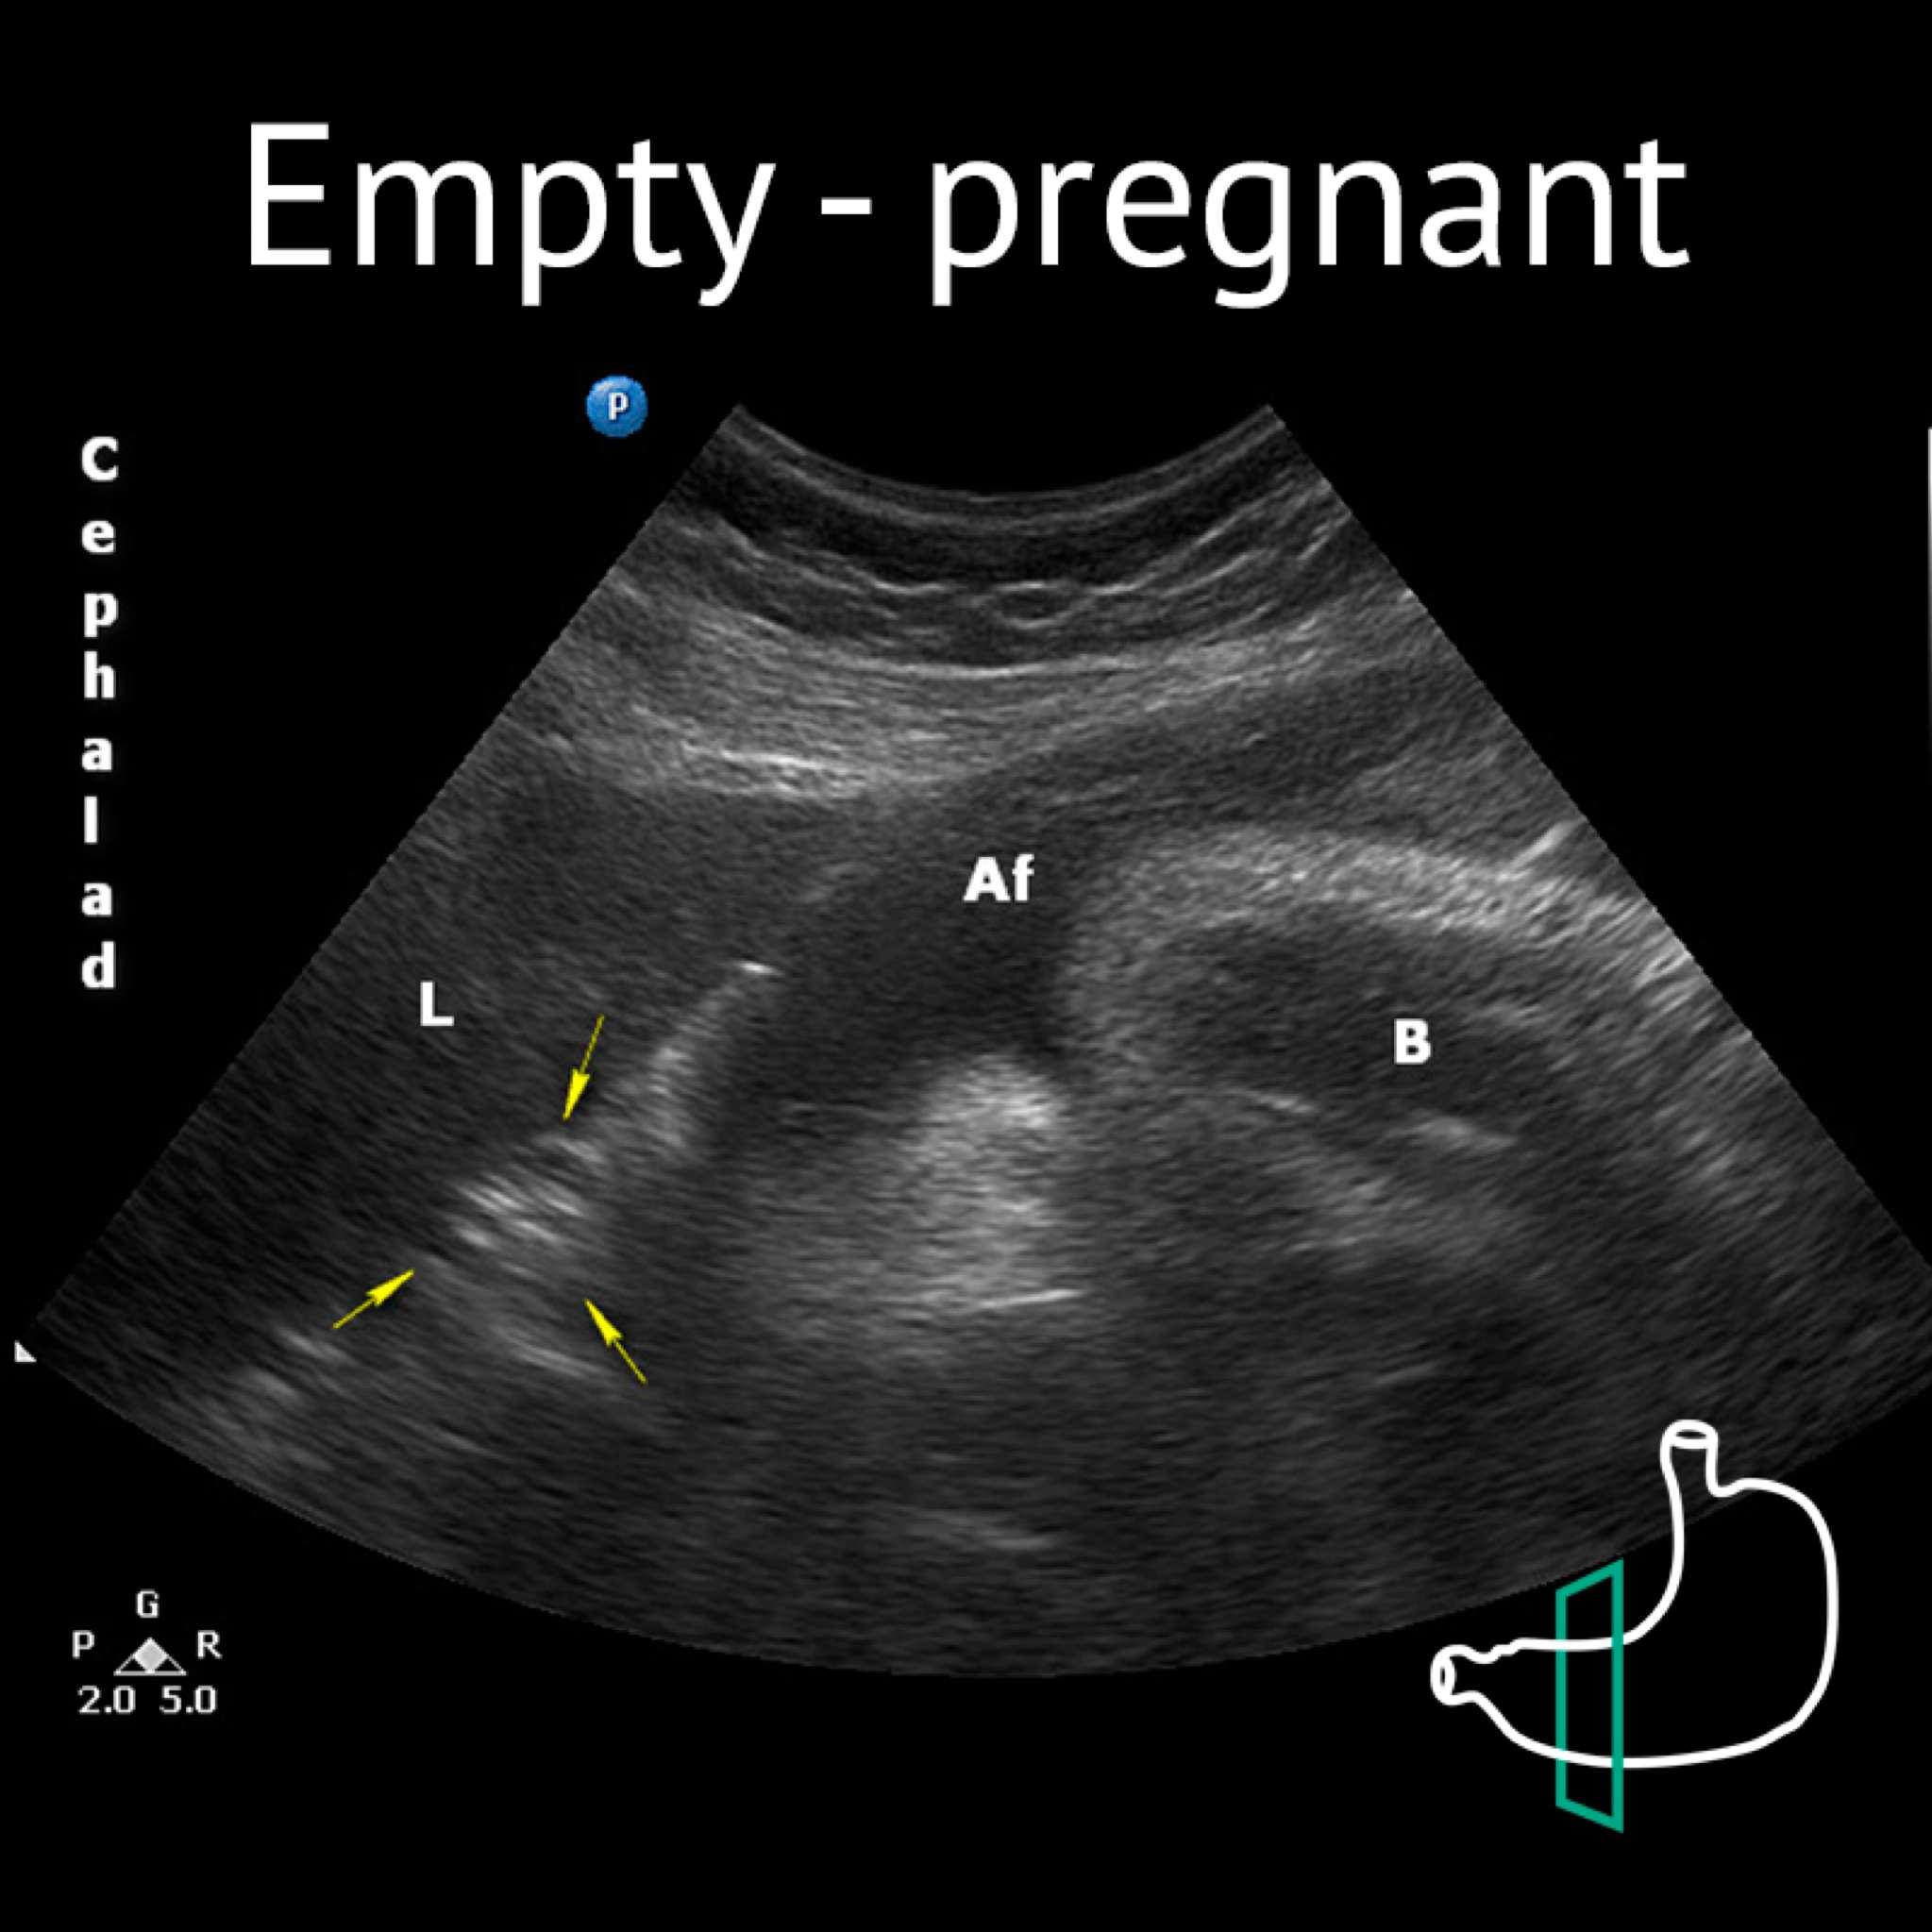

Af: amniotic fluid; B: baby; L: liver; Yellow arrows: antrum